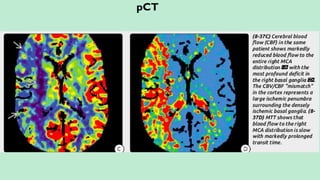

pCT

pCT inVarious Areas of Brain: MTT:

Grey Matter (BG and Cortex) – Red/Yellow. Slow – Red.

White Matter – Blue. Normal – Blue.

Ischemia – Blue/Purple and Infarct/CSF – Black.

Infarct Core (Irreversibly Damaged Brain):

a. Matched Perfusion (CBV and CBF – both decrease).

b. Increased MTT.

Ischemic Penumbra:

c. Perfusion Mismatch (Normal CBV, decreased CBF).

Penumbra = CBV – CBF.

Prolonged MTT (145%) beyond infarct core i.e. CBV/MTT mismatch = Penumbra.

FLAIR – DWI Mismatch = Penumbra.